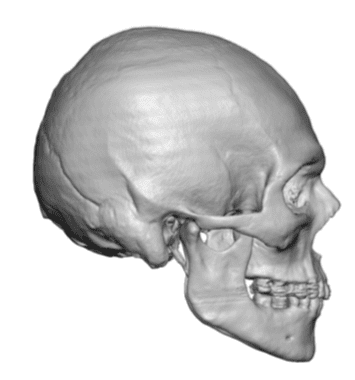

Male with congenital sagittal skull deformity with a long and narrow head.

Custom skull implant to widen the head from front to back with forehead and occipital skull bony reductions.

Male with congenital sagittal skull deformity with a long and narrow head.

Custom skull implant to widen the head from front to back with forehead and occipital skull bony reductions.